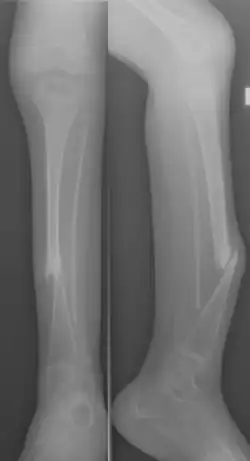

Eine kongenitale oder infantile Tibiapseudarthrose (lat. Crus varum congenitum, engl. Congenital pseudarthrosis of the tibia) stellt eine seltene Sonderform einer Pseudarthrose am Unterschenkel dar, welche sowohl die Tibia als auch die Fibula sowie die begleitenden Weichteile betrifft und häufig bei Patienten mit Neurofibromatose auftritt.[1]

Im Grunde handelt es sich um eine zunehmende Verkrümmung der Unterschenkelknochen mit Infraktionen oder Frakturen, die nicht ausheilen, sondern eine Tendenz zum Ausdünnung der Kompakta und Knochenrückbildung aufweisen. Betroffen ist in der Regel das mittlere und/oder distale Drittel der Tibia.[2] Die Pseudarthrose ist entgegen der so üblichen Bezeichnung nicht angeboren, lediglich die Neigung dazu.[1]

Je nach Ausprägung der radiologisch fassbaren Veränderung kann eine Klassifikation erfolgen, z. B. nach Crawford[4]

- Typ I crus antecurvatum, nur Antekurvation und Kortikalisverdickung

- Typ II crus varum et antecurvatum, Antekurvation + Varusverbiegung + Sklerosierung

- Typ III zystische Strukturveränderung wie bei Fibröser Dysplasie, Frakturen im 1. Lebensjahr

- Typ IV dysplastisch, Knochen ausgedünnt, sklerosiert, verschmächtigt.

Leitsymptom ist Antekurvation und Beinverkürzung des Unterschenkels, die Diagnose wird mittels Röntgenbild gestellt. Die Erkrankung wird bereits in den ersten Lebensjahren auffällig[5]